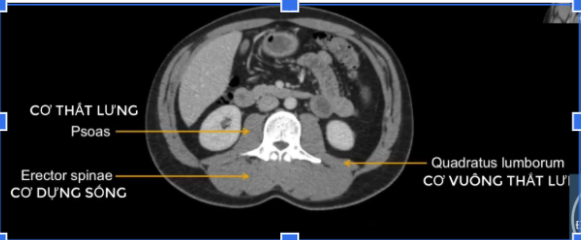

cơ tl? cơ chậu?